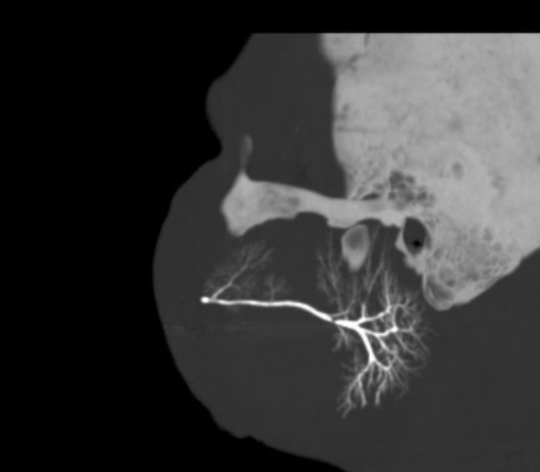

How do you investigate for ?sialolithiasis? [1]

Investigation involves sialography to demonstrate the site of obstruction and associated other stones